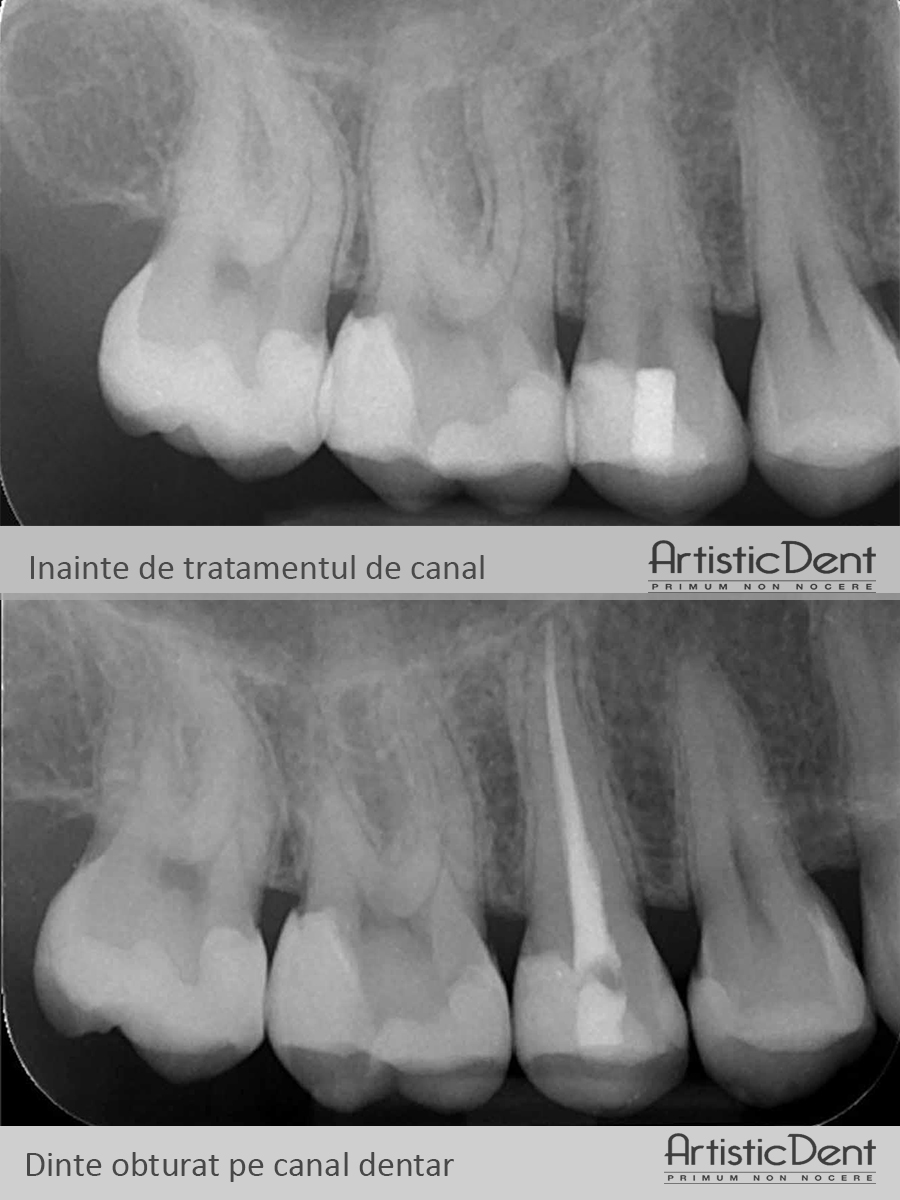

The images below will help you get an idea of what the canal treatment of an infected tooth is.